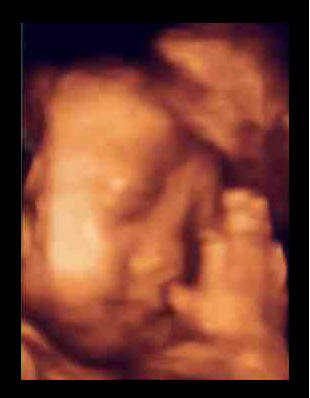

左は、9週目の「私」。右は29週になった「私」。

下の写真を見比べてみて。今までのエコー写真は白黒で、シルエットがぼんやり写るぐらい(左写真)。右の4D写真だと、「私」の手の指も、顔の輪郭も、臍帯まではっきり見えるでしょ?

先生の説明だと、モノが立体に見える「3D画像」を時間を追ってみられるから「4D」と呼ぶんだそうです。1秒間に6回画像が更新されて、映像を見ているみたいにリアルなんだって。手で顔をこすったり、あくびをしたり、足を握ったリ、キックしたり。しかめ面や微笑む顔まで、よーくわかるらしいの。ママの臍帯を握って安心している様子も見られちゃう(下写真)。ママは「ああ、お腹の中で生きてるんだなあ」って実感がわいて、とても感動するみたい。